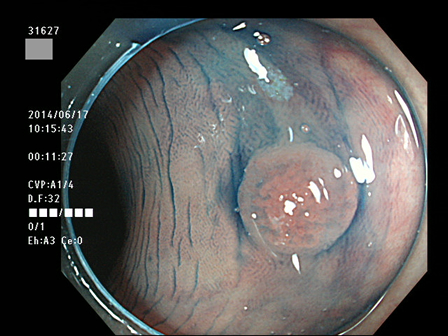

31600 31601 31603 31604 31606  31607 31610 31611 31612 31616 31623 31624 31625 31627 31630 31631 31632 31638 31639 31640 31641 31642 31644 31645 31646 31649 31650 31653 31656 31658 31659 31660 31661 31662 31665 31666 31667 31670 31671 31672 31673 31674 31676 31679 31680 31683 31684 31687 31689 31691 31693 31694 31696 31697 31699 ・・・・の55名

上記100名より抽出した平坦・陥凹型腺腫(=癌化の危険が高いが見落としやすい病変)の内視鏡写真